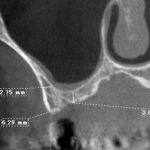

1ミリ以下の薄い骨でも大丈夫

ラテラルスリット法ではすべての骨の厚さに対応することができ、インプラント治療で大事な初期固定も十分確保することができます。骨が薄すぎてインプラント治療は無理ですといわれた方、大学病院での移植などを勧められた方。一度当歯科医院にご相談においでください。